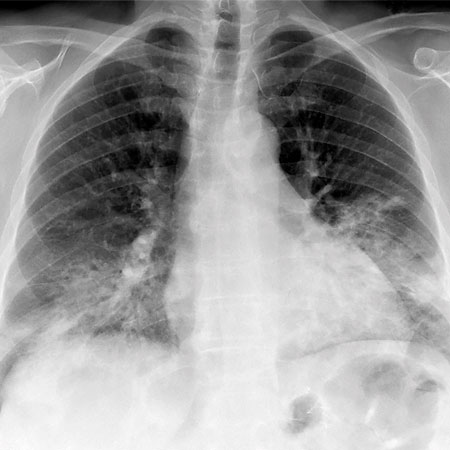

Fallbeskrivning En sars-cov-2-infektion kan ha utlöst den inflammatoriska kaskad som ledde till diagnosen MOG-antikroppssjukdom